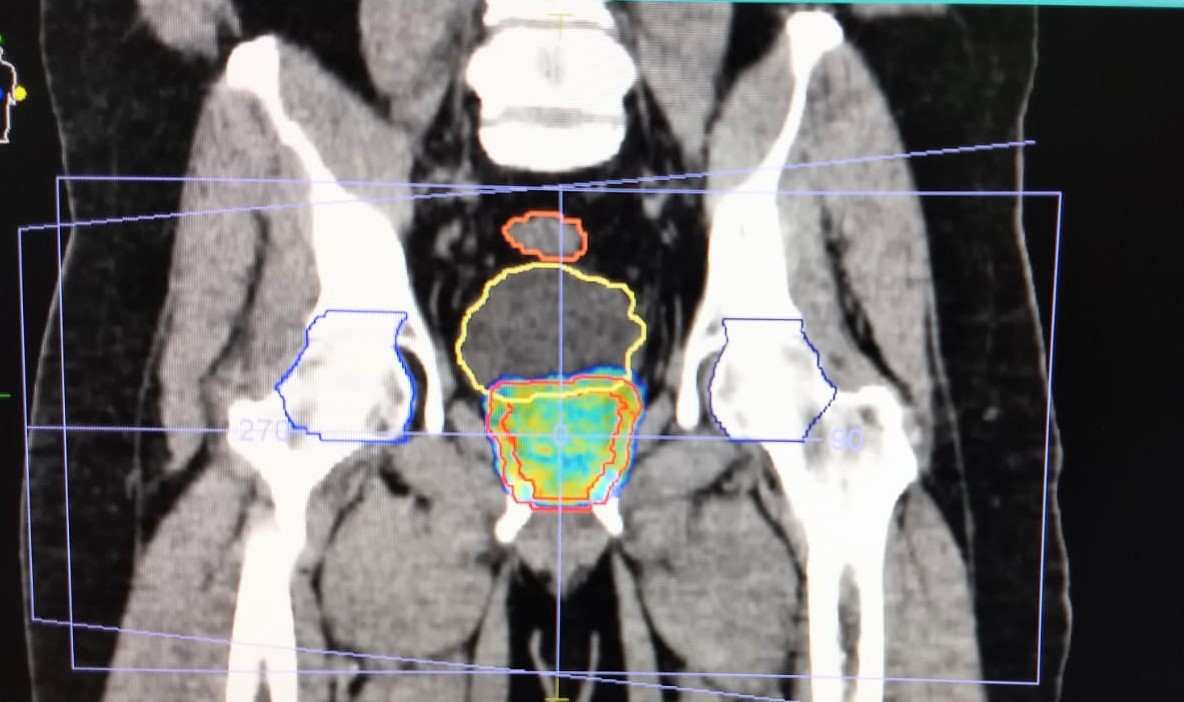

O Centro Regional Integrado de Oncologia tem oferecido soluções avançadas a pacientes com câncer. As últimas inovações tecnológicas são utilizadas nas sessões de radioterapia e radiocirurgia. Um exemplo disso foi a mais recente radiocirurgia de próstata com o recurso do Acelerador Linear Versa. O procedimento foi realizado com uma alta dose por dia, modulação da intensidade do feixe e controle de qualidade por imagens, sendo possível reduzir o tempo total de tratamento de oito para apenas uma semana.

Com a modulação do feixe é fornecida uma dose de radiação mais pontual em conformidade ao tamanho, volume e formato do tumor alvo, preservando órgãos e tecidos normais. "A radiocirurgia de próstata é um tratamento inovador, preciso e tão eficaz e seguro quanto o convencional, mas com a grande vantagem de ser realizado em menos tempo", afirma o radioterapeuta Mauro Rosalmeida.

Outra grande vantagem (exclusiva do AL Versa em Fortaleza) é a maior velocidade de entrega da dose de radiação diária (Free Flattening Filter - FFF), que minimiza o risco de movimentação do alvo durante a aplicação. Simbora lá?